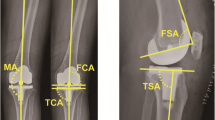

A standardised radiographic assessment was performed to confirm the absence of malrotation in the radiographs (antero-posterior view, both the proximal tibia and fibula can be seen and are not overlying significantly; lateral view, the condyles of the femoral implant are overlying one another). X-rays were taken 1 week after surgery and included a total lower limb X-ray in a weight-bearing position, an antero-posterior view, and a lateral view. The assessor measured the HKA, frontal femoral component angle (FFC), frontal tibial component angle (FTC), lateral femoral flexion angle (LFF), and lateral tibial component angle (LTC) (Fig. 2). Calculations were completed to determine the absolute deviations of the HKA, FFC, FTC, LFF, and LTC from the ideal parameters (HKA, 180°; FFC, 90°; FTC, 90°; LFF, 87°; and LTC, 83°). The objectives used in this study were as follows: [1] restoration of an HKA value of 180° ± 3°, [2] satisfactory FFC and FTC defined as 90° ± 3°, [3] satisfactory LFF defined as 87° ± 3°, and [4] satisfactory LTC defined as 83° ± 3°. The radiographs were assessed twice by one experienced orthopaedic surgeon (CZH) who was not participated in surgery and blinded to the group to which the patient belonged using the IMPAX 6 (Agfa-Gevaert N.V., Mortsel, Belgium). To test intra-observer reliability, each set of measurements was repeated three times on 30 randomly selected patients. The intra-observer reliability based on ICC ranged from 0.878 to 0.901. All abovementioned parameters were compared between the two groups. The primary outcome of this evaluation was the proportion of radiological angle within 3° for HKA, FFC, FTC, LFF, and LTC, while the secondary outcomes include the absolute deviations of the HKA, FFC, FTC, LFF, and LTC.